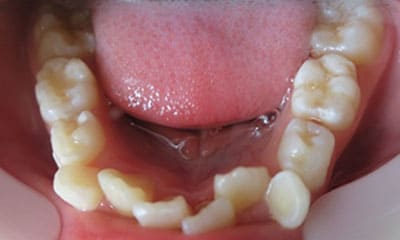

● C4を超え歯根までの虫歯を抜歯、親知らずを利用して歯並び全体を整えた症例

藤沢デンタルオフィスの虫歯や破折で抜歯後の部分矯正